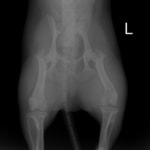

症例3:キルシュナーワイヤーのピンニングによる整復

ペルシャ猫 11ヶ月齢 雄

他院にて左大腿骨遠位の成長板骨折(salter-harrisⅠ型)が認められており、治療相談を目的として来院。当院にて、キルシュナーワイヤーを用いたピンニングにより骨折部位の整復を行いました。術後の経過は良好で、現在も経過観察中です。

術前レントゲン